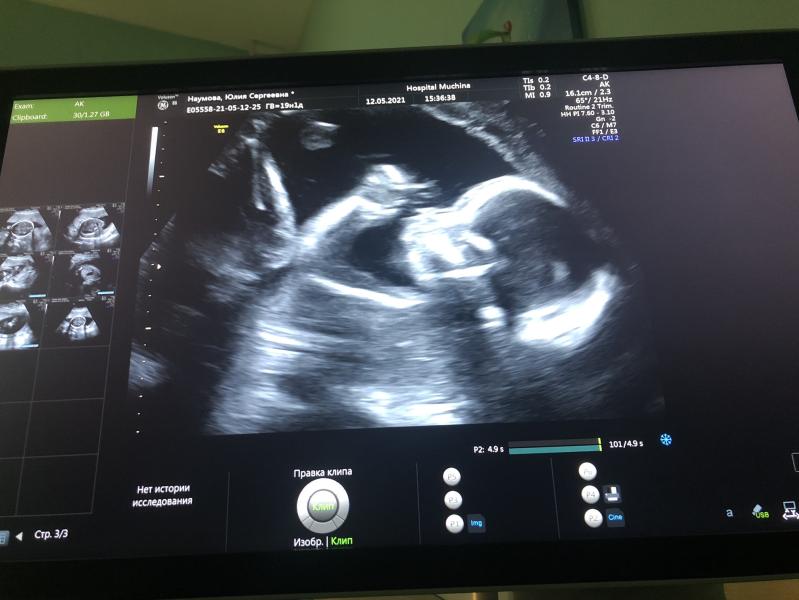

2 скрининг- 19 нед. 4 дня пройден

С нашим сыночком все хорошо🙏🏻 . В третий раз подтвердили мальчика💙

Вес малыша 300 грамм

Развивается по сроку

Шейка 35мм , количество вод в норме.